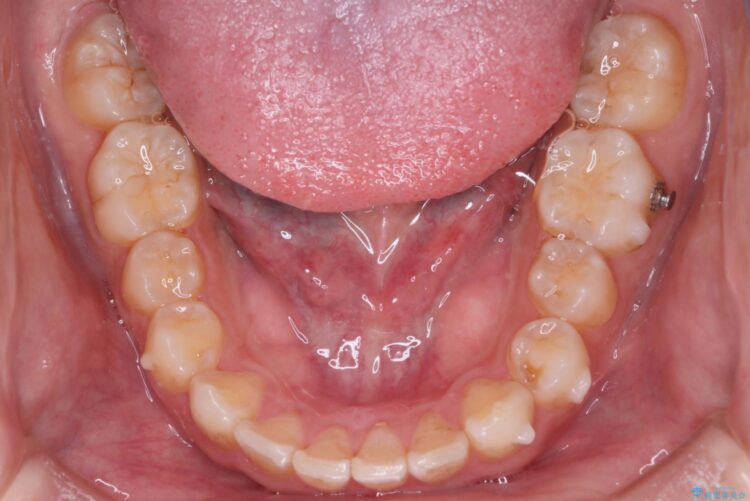

前歯の叢生と口元を下げたいとのことでご来院されました。

その上で今回は抜歯を行わず、歯の表面をわずかに整えるIPRを活用しながら、インビザラインで前歯のガタつきを優先的に改善していく計画を立案しました。

インビザライン矯正により、前歯のガタつきが改善されました。